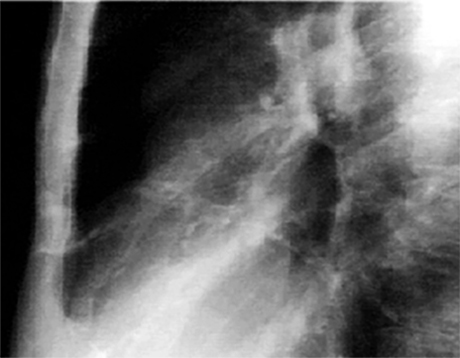

This chest X rays show calcified coronary arteries. The lateral view is often best for demonstrating calcium in the coronary vessels. Calcifications are much more common in the proximal parts of the vessel, usually within 2 cm of the root of the aorta and reflect coronary atherosclerosis. In this enlargement of the lateral view, the railroad track shadows of calcium are more easily seen.